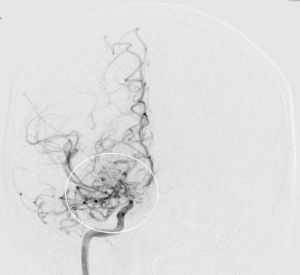

Angiografie einer Moymoya

Auf dem Bild mit einer Gefäßdarstellung “Angiographie” kann man die dünnen Kollateralen (Wolken-ähnliches Bild) um die Gefäßengstelle am Ende der inneren Halsschlagader erkennen.